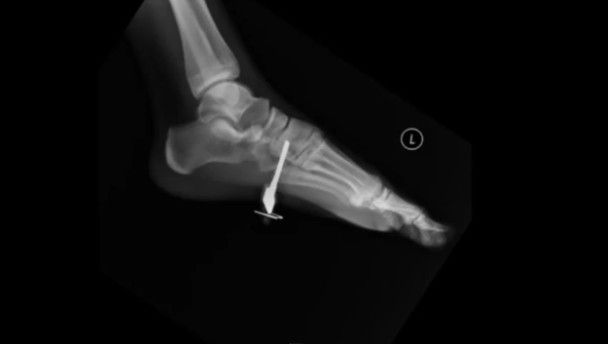

“The chances were one in a million. My reaction was pretty anti-climactic. I was then taken to the emergency room where they took X-Rays to make sure the key did not fracture a bone or damage any nerves. Thankfully it did not, and I got it removed a few hours later.”